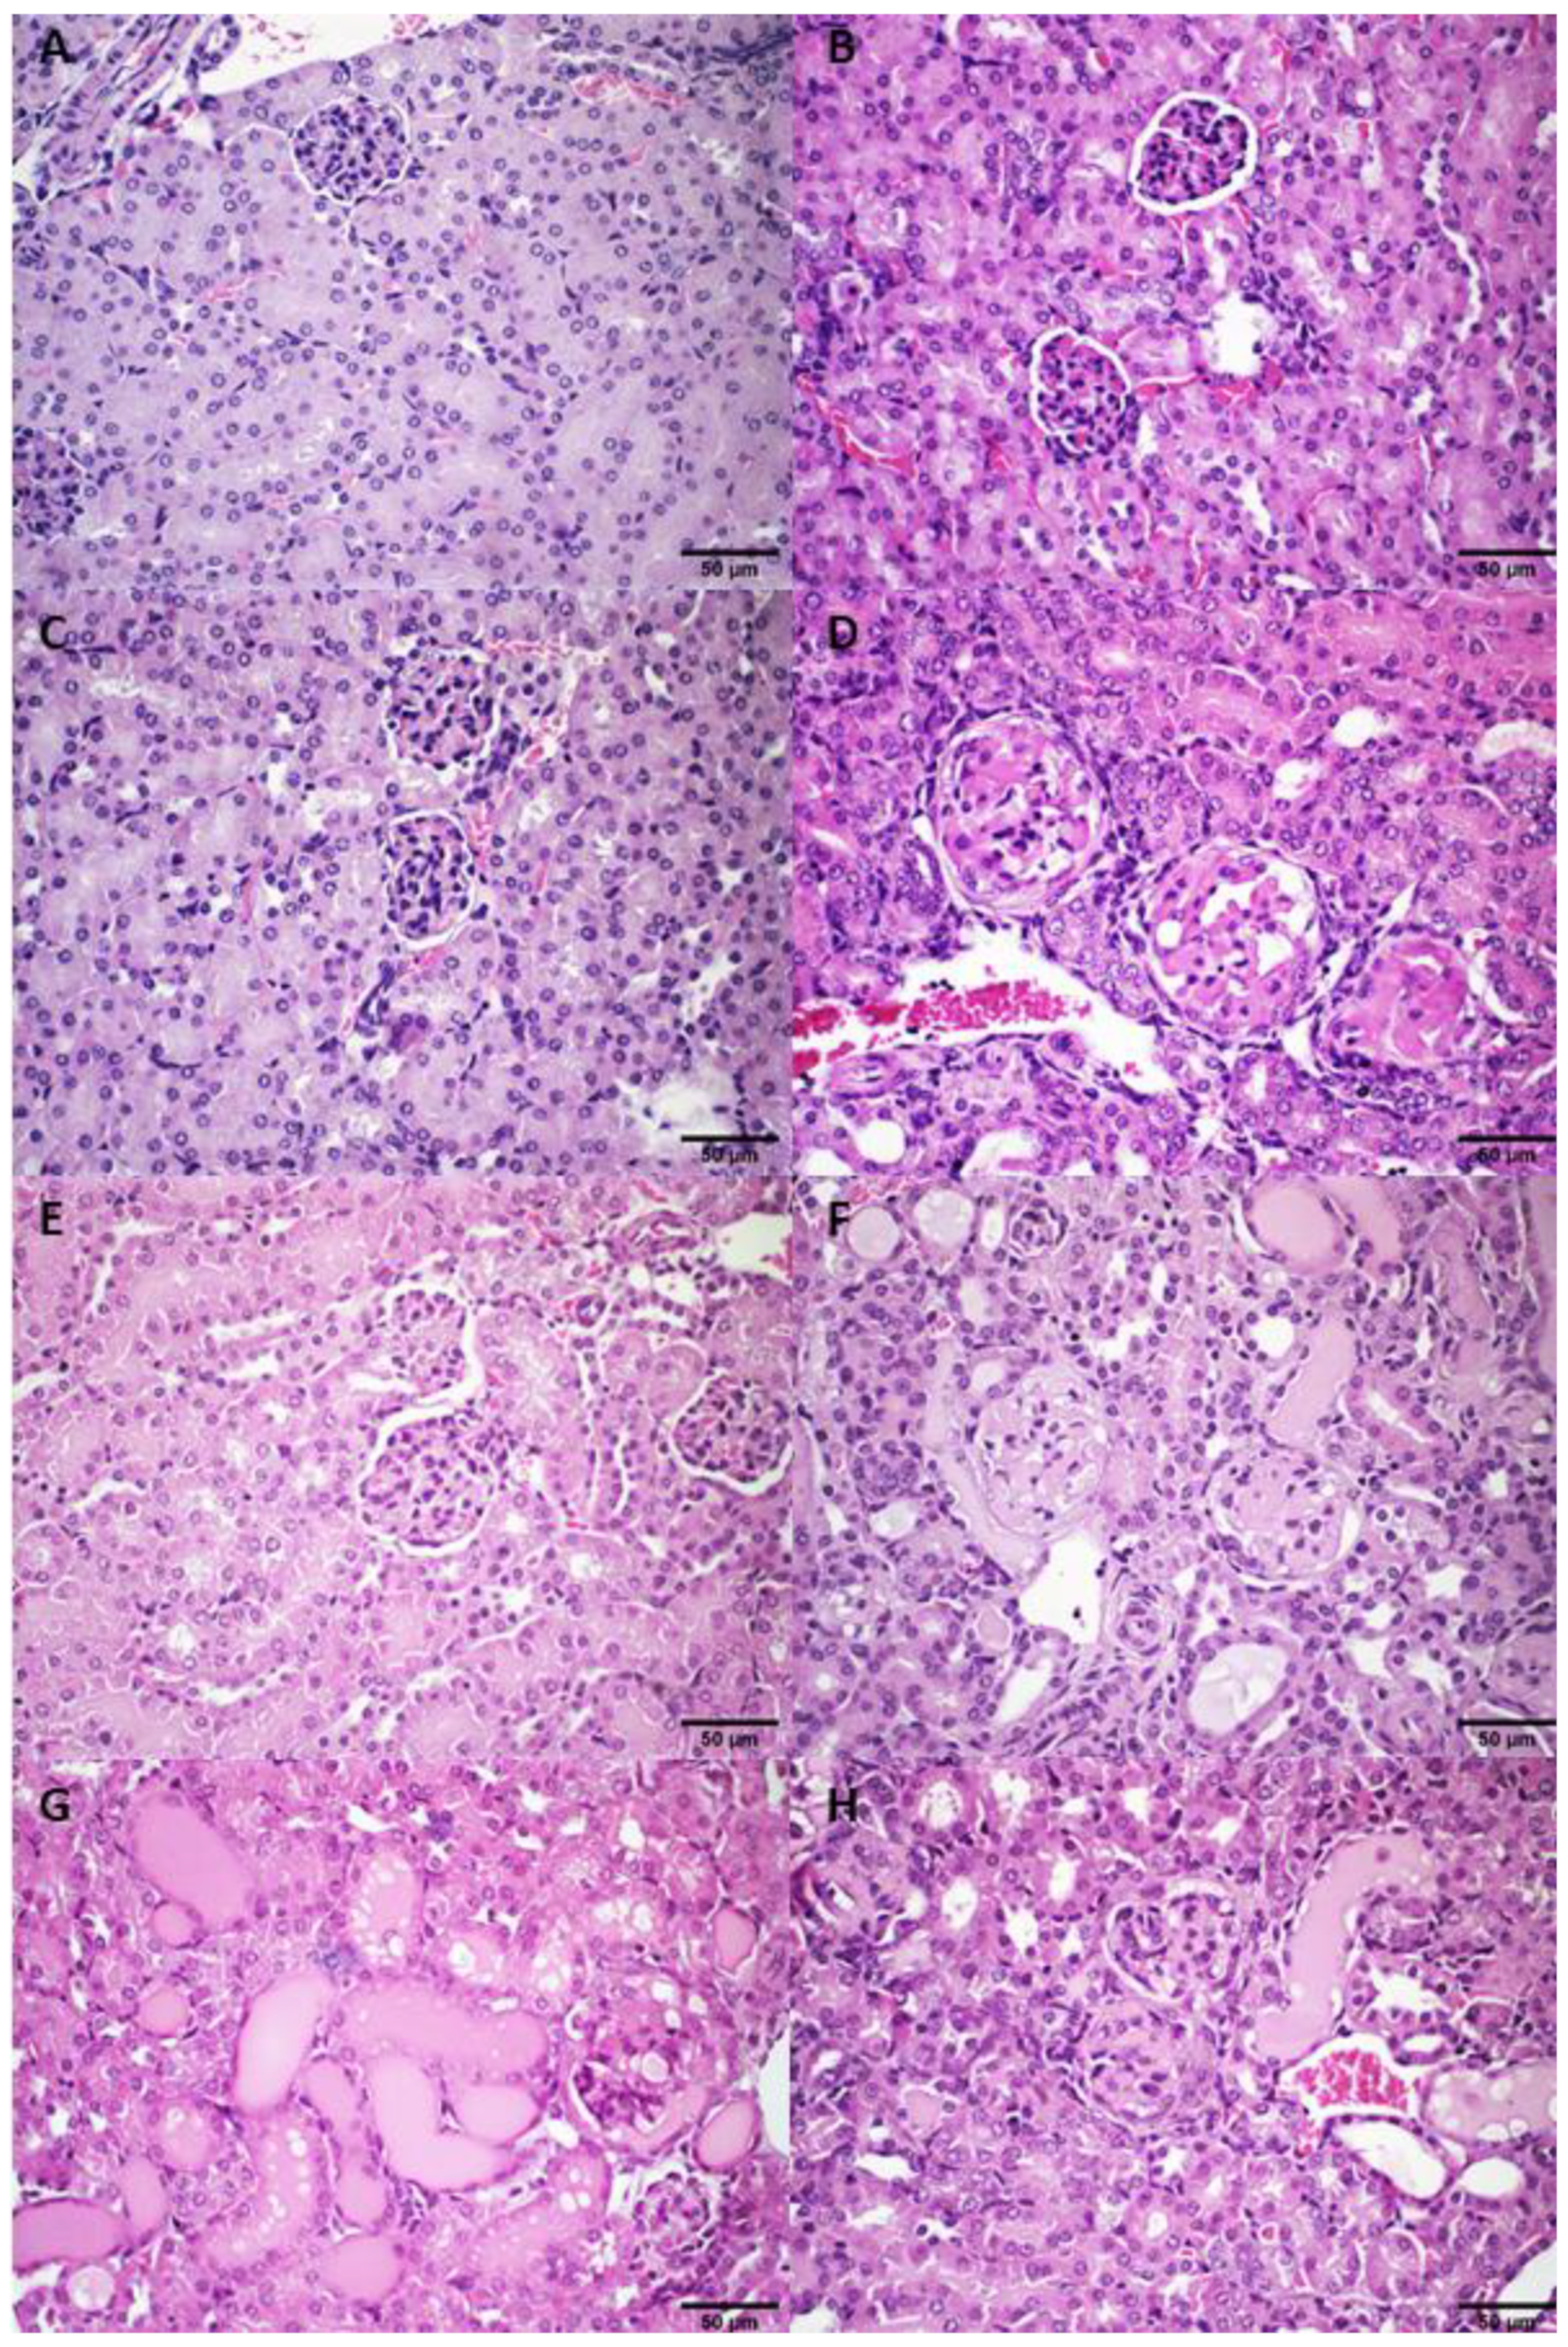

3.2.4. Histological Analysis

3.3.2. Histological Analysis